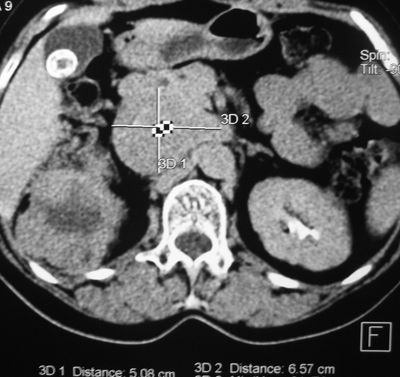

Компьютерная томограмма